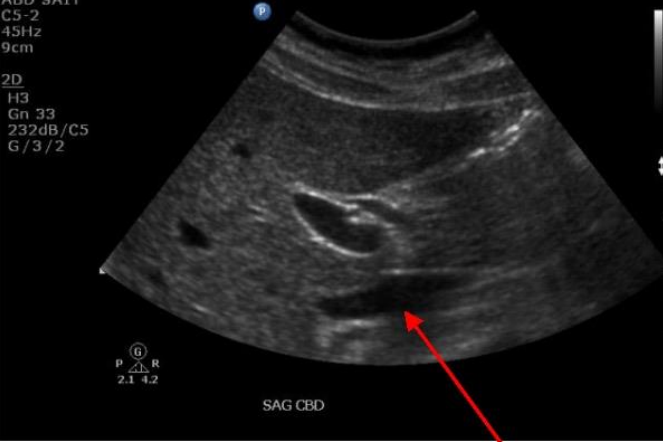

17

Q

Label the red arrow